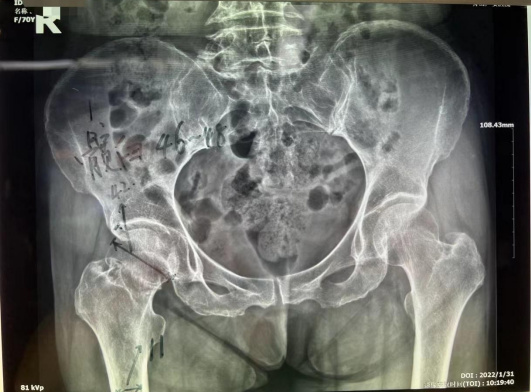

家住普陀的鄭阿姨今年70歲,大年初一在路上行走時(shí)不慎被電動(dòng)車撞倒,右髖部當(dāng)即動(dòng)彈不得。當(dāng)即被家人送來(lái)我院就診。門診拍片診斷為右股骨頸骨折,由于保守治療導(dǎo)致股骨頭壞死、骨折端不能生長(zhǎng)的可能性極大。而且長(zhǎng)期臥床也容易引發(fā)褥瘡、深靜脈血栓、肺部感染等并發(fā)癥。醫(yī)生建議其行全髖關(guān)節(jié)置換術(shù)。

患者為右股骨頸骨折